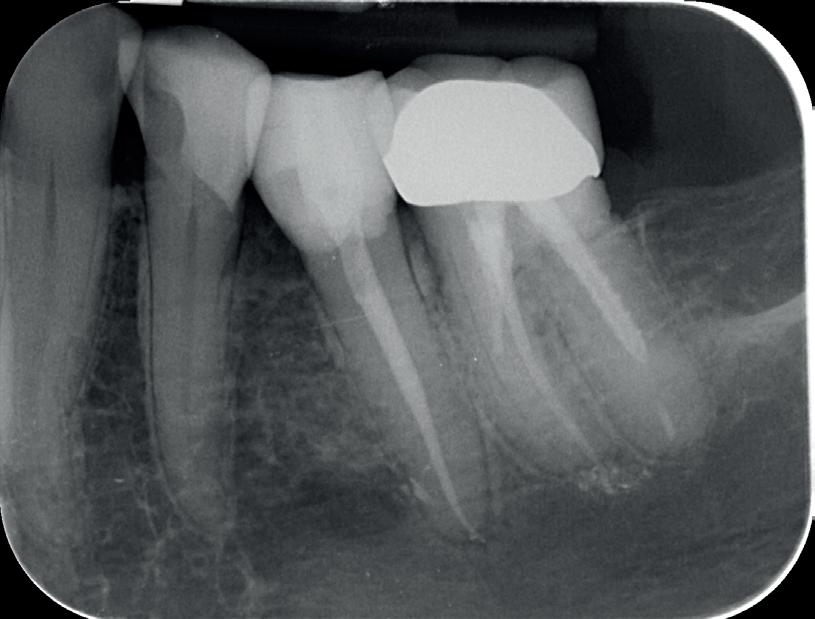

Naast de geavulseerde 21, hebben we ook nog te maken met een horizontale fractuur van element 11. Deze is na ongeveer 7 uur gediagnosticeerd, gerepositioneerd en gespalkt.

Bij een horizontale wortelfractuur hangt de overleving van het element af van de locatie van de fractuur. Is deze erg ver naar apicaal, dan is de overleving erg goed. Als de fractuur ver naar coronaal ligt een stuk minder. Dit wil nog niet meteen zeggen dat het element verloren is. Er ontstaat alleen een element met een zeer korte wortel. De naam ‘horizontale’ wortelfractuur is eigenlijk niet correct. Er is nagenoeg altijd sprake van een ‘schuine’ fractuur (foto 7).

De behandeling van elementen met deze fractuur bestaat uit het coronale deel weer in de goede positie te plaatsen. Spalken is alleen nodig als het coronale deel erg mobiel is.

Er zijn vervolgens vier mogelijke scenario’s:

A. Er vormt zich hard weefsel tussen de breukdelen.

B. Er vormt zich aanhechtingsweefsel (PDL) tussen de breukdelen.

C. Er groeit bot en PDL tussen de breuklijnen.

D. Het coronale deel van de pulpa wordt necrotisch

en er ontstaat een ontsteking tussen de breukdelen (foto 8).

Het scenario waarbij er een necrotische pulpa ontstaat ligt op ongeveer 25%. De voorkeur heeft het dus om en afwachtend beleid in te stellen.7

Meteen na het ongeval is gecontroleerd of de patiënt nog beschermd was tegen tetanus. Ik bespreek de ontstane gebitssituatie; een tot voor kort volledige gave dentitie. Nu een 11 met een horizontale wortelfractuur en een gereplanteerde 21 met een necrotische pulpa. De pulpa van element 11 reageert positief op de koudetest. Uiteraard wordt er een afwachtend beleid in gesteld.

Een afspraak voor over drie weken wordt gemaakt om de spalk te verwijderen en de endodontische behandeling af te maken. Het advies is om de elementen weer normaal te gaan gebruiken en alles zeer goed te poetsen. Door het ‘normale’ gebruik bewegen de elementen en dit bevordert de genezing. Hetzelfde advies als na een autotransplantatie van een gebitselement (foto 10 en 11).

Drie maanden later is er een afspraak bij de implantoloog om de situatie te beoordelen. Er zijn nagenoeg geen klachten en het bovenfront kan normaal gebruikt worden (foto 12). Element 21 klinkt ankylotisch, wat uiteraard niet zo gek is. Als er meer dan 20% ankylose is, hoor je een “metaalachtig” geluid. Meestal is het pas in een later stadium zichtbaar op een solo. Hierop kun je alleen het mesiale en distale gedeelte van de wortel zien.